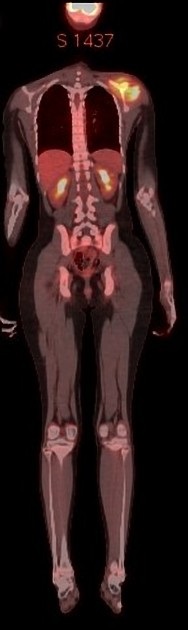

La

scintigraphie osseuse et PET CT sont

utile pour chercher la multiplicité ou non de l'atteinte

osseuse